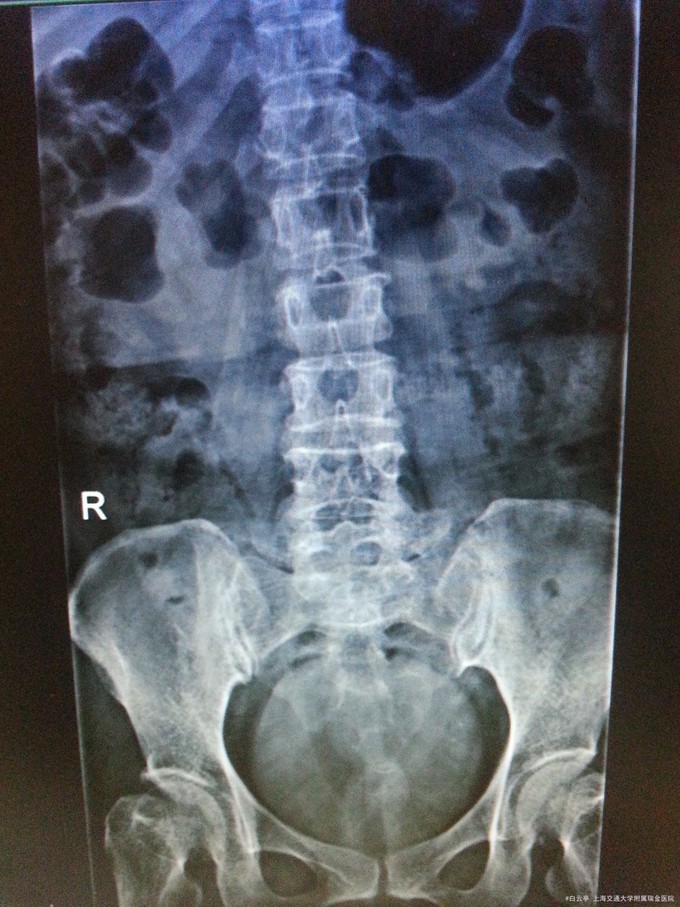

主诉:跌倒后腰痛10日 病史:患者,女,68岁。患者10天前站在意外从小板凳上摔倒后出现腰背疼痛伴活动受限,患者诉站立及坐位时腰痛加剧,卧床时可缓解。在当地医院行保守治疗后上述症状未缓解。于外院行腰椎CT示:L2椎体压缩性骨折;腰椎退变。患者为行进一步诊治而来我院,门诊拟“骨质疏松性腰椎骨折”收治入院。

查体:无脊柱侧弯、畸形;腰段压痛及叩击痛,以L2椎体附近为重,未引出下肢放射痛。髂骶关节及骶尾骨后方无压痛,双侧4字试验阴性,双侧屈膝屈髋试验阴性。双下肢直腿抬高试验:右70度,加强试验阴性;左70度,加强试验阴性。腰功能活动受限。 辅检: 1.腰椎正侧位片:腰椎侧弯变直,L5椎体向前轻度滑脱;L2椎体楔形变;腰椎退行性改变。 2.椎体三维重建:L2椎体压缩性骨折,椎管无狭窄;腰椎侧弯变直,L5椎体向前轻度滑脱;腰椎退行性改变;腰椎骨质疏松。

诊断:骨质疏松性腰椎骨折(L2) 治疗:行“腰椎骨折后凸成形术(L2)”,术后加强预防骨折疏松治疗